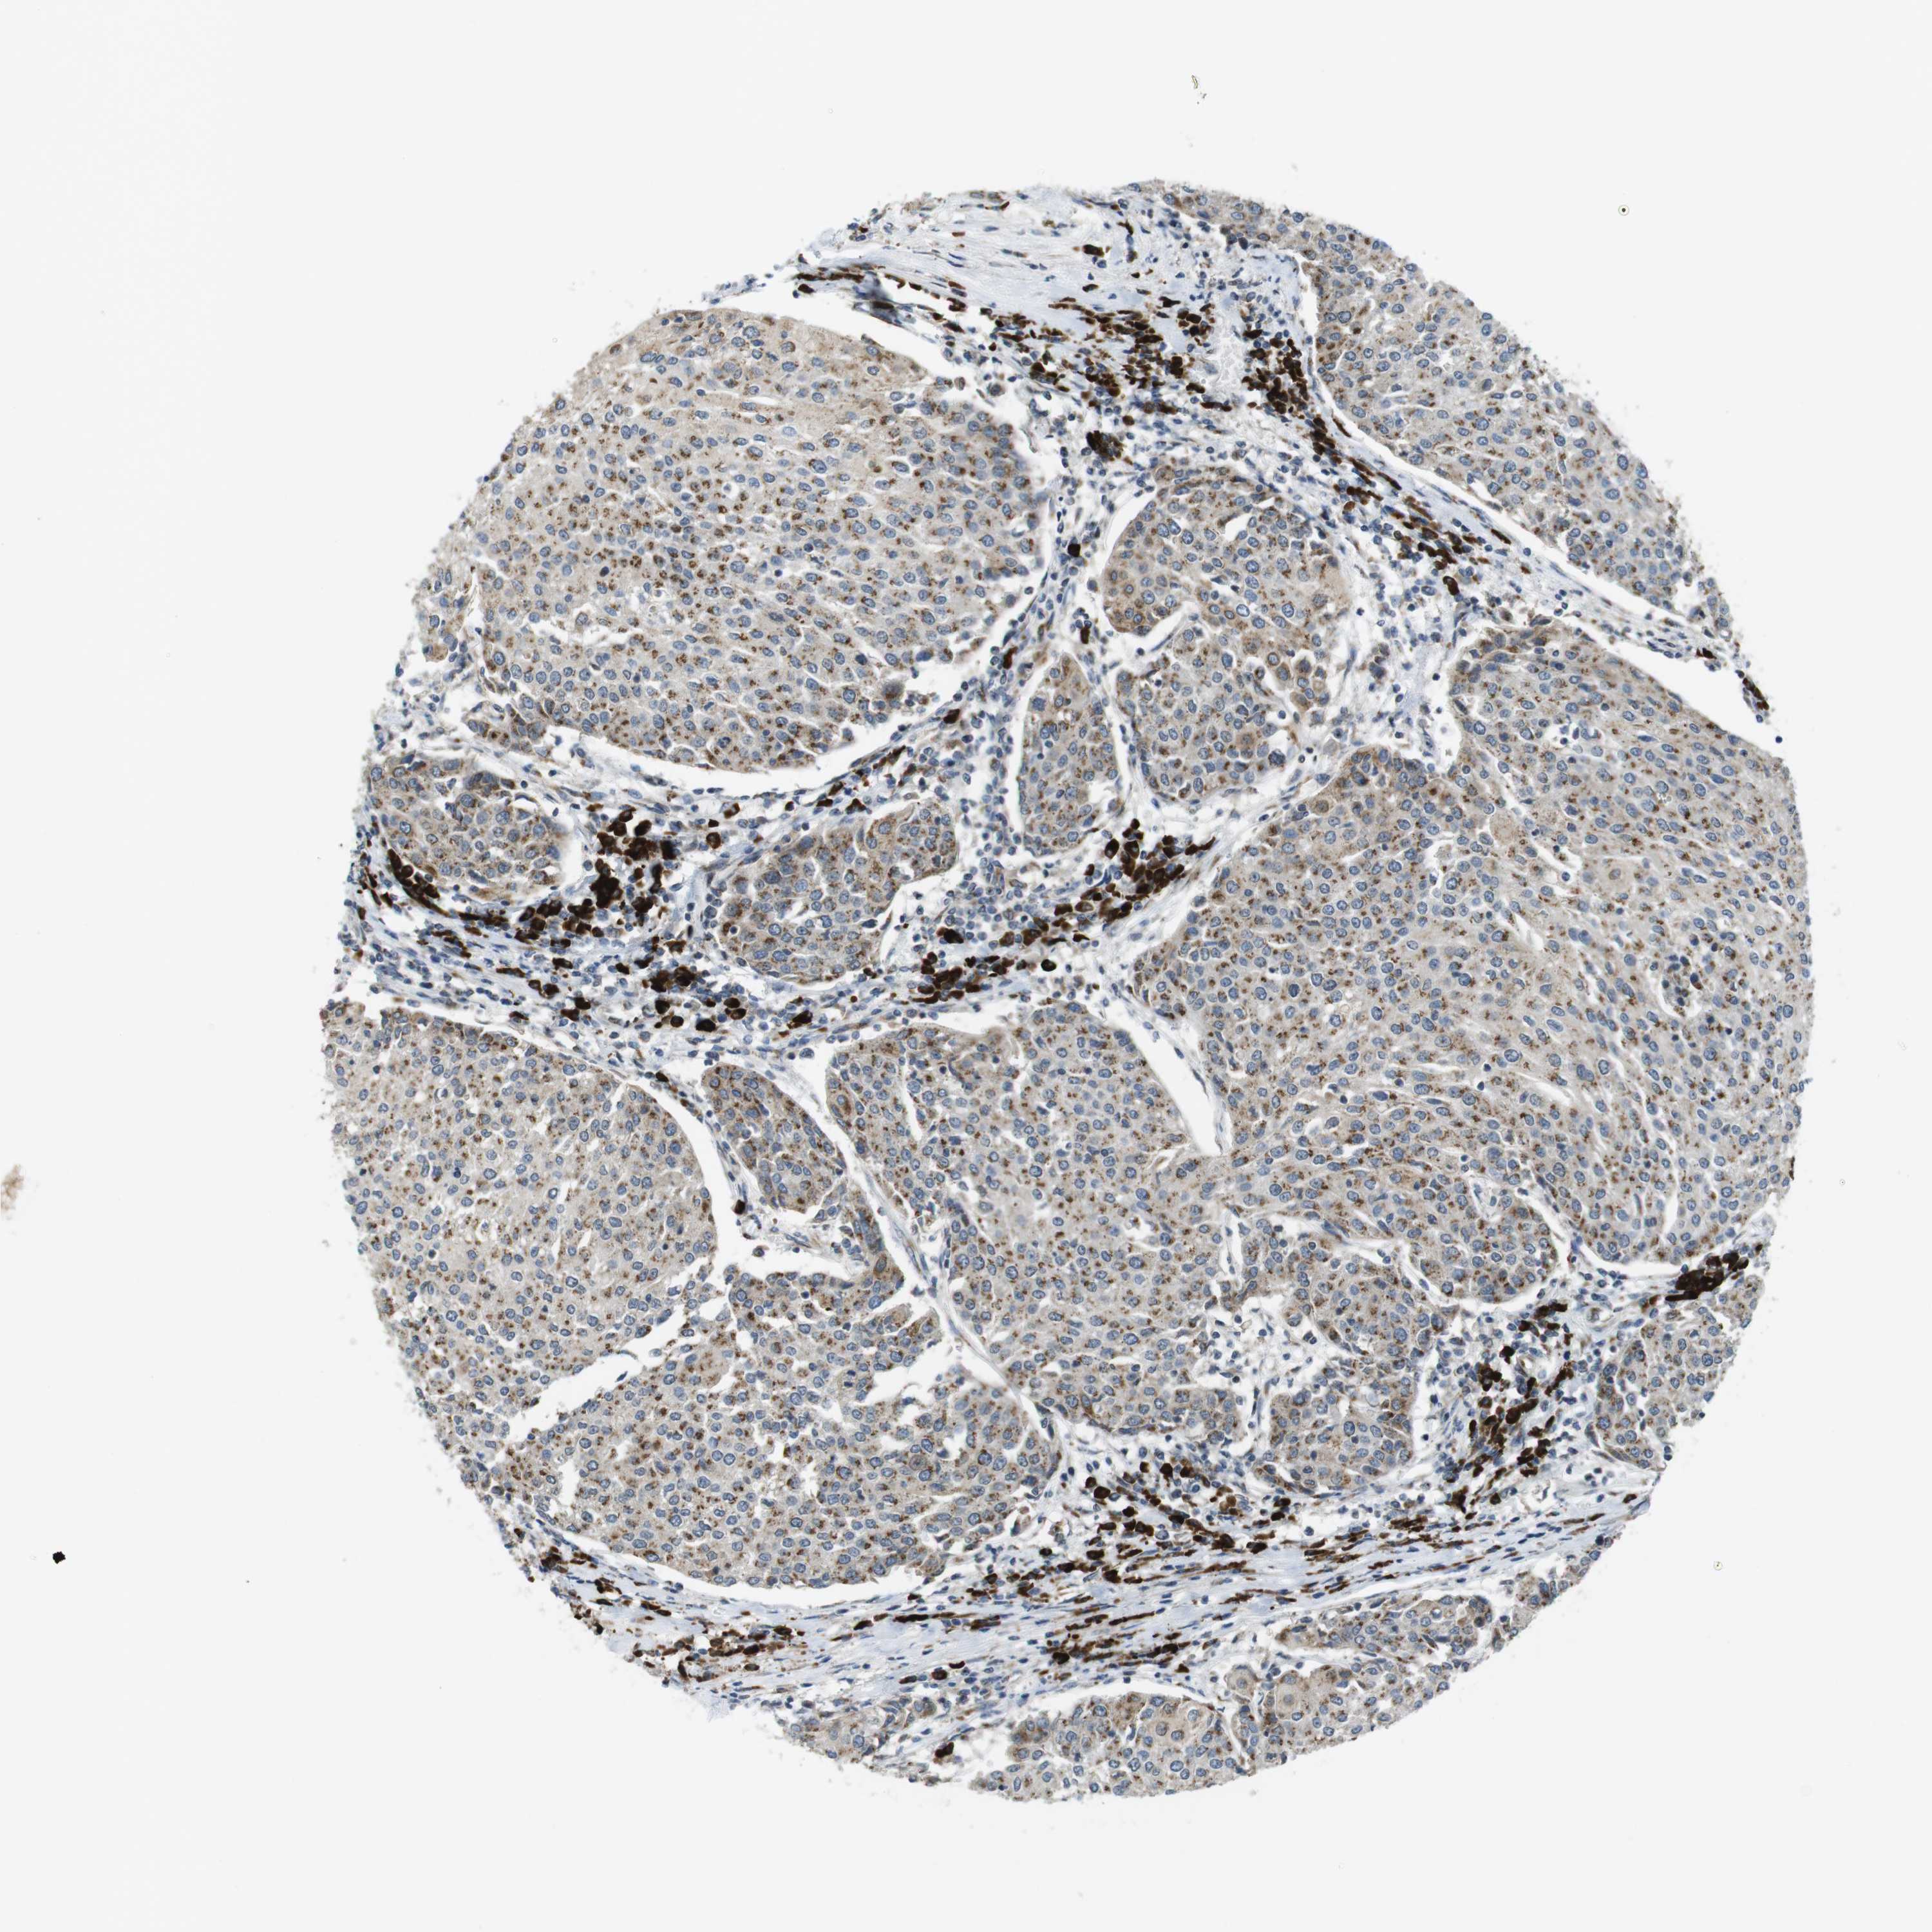

UROTHELIAL CANCER - Protein expressioni

A mouse-over function shows sample information and annotation data. Click on an image to view it in a full screen mode. Samples can be filtered based on level of antibody staining by selecting one or several of the following categories: high, medium, low and not detected. The assay and annotation is described here.

Note that samples used for immunohistochemistry by the Human Protein Atlas do not correspond to samples in the TCGA dataset.

Antibody stainingi

Antibody staining in the annotated cell types in the current human tissue is reported as not detected, low, medium, or high, based on conventional immunohistochemistry profiling in selected tissues. This score is based on the combination of the staining intensity and fraction of stained cells.

Each image is clickable and will lead to virtual microscopy that enables deeper exploration of all samples and also displays staining intensity scores, fraction scores and subcellular localization as well as patient and tissue information for each sample.

Antibody HPA014909

Antibody HPA017347

Staining

High

Medium

Low

Not detected

Intensity

Strong

Moderate

Weak

Negative

Quantity

>75%

75%-25%

<25%

None

Location

Nuclear

Cytoplasmic/membranous

Cytoplasmic/membranous,nuclear

Urothelial carcinoma, Low grade

Urothelial carcinoma, High grade